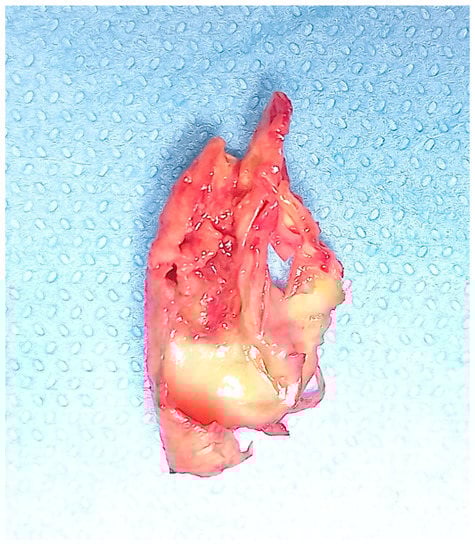

All the included patients gave informed consent for the procedure itself, anonymous data collection, and analysis. The study was performed in agreement with the Declaration of Helsinki, and the STROBE guidelines for reporting observational studies were followed [10]. All participants underwent baseline clinical examinations, which included medical history and physical examination. The initial diagnosis assessment included a DUS (model SSA-270A; Toshiba America Medical Systems, Tustin, Calif). The longitudinal image of the carotid artery bifurcation, the internal carotid artery and two traversal images of the CCA of all patients were acquired. The maximal CCA IMT was defined as the mean between the maximal IMT on both CCA left- and right-side images. The IMT was defined as the distance between the near and far walls. Native vessel assessment parameters for DUS included peak systolic velocity (PSV), IMT measurement, and plaque morphology evaluation. Surface characteristics were classified as smooth, irregular, ulcerated (if there was a depression of >2 mm into the media), soft (hypoechoic or isoechoic due to a prevalent component of lipids), and calcified. In patients presenting a carotid artery plaque, degree of stenosis was evaluated according to the ECST method (Figure 2) [11].

Figure 2.

Ulcerated carotid plaque after endarterectomy.

In this study, the assessment of hemodynamically significant stenosis was completed with a cerebral CT scan and a CT angiography in the case of stenosis >70% in order to confirm and to objectively evaluate the plaque and its features. In the literature and in our experience, in addition to the degree of luminal stenosis, the plaque composition is also essential to evaluate and discuss. From mild fatty deposition in asymptomatic patients to complex, irregular plaques prone to the thromboembolism, DUS, CT scan, and high-resolution MR can provide significant information [34,35]. DUS is useful in determining hemodynamic features; Choi E. et al. report how CT scans help to assess the composition of plaque, with Hounsfield unit density and spotty calcium considered independent predictors of a greater risk of adverse cardiovascular event occurrence; Porambo ME et al. underline the ability of MR in the study of vulnerability plaque showing thoroughly lipid-rich necrotic core, thin/ruptured fibrous cap, and intraplaque hemorrhage, predicting factors of future stroke [36,37]. However, every imaging method can be a source of information about carotid plaques with DUS representing the first line of approach to CAAD, and CT scans and MR are useful tools to identify patients with high risk [38].